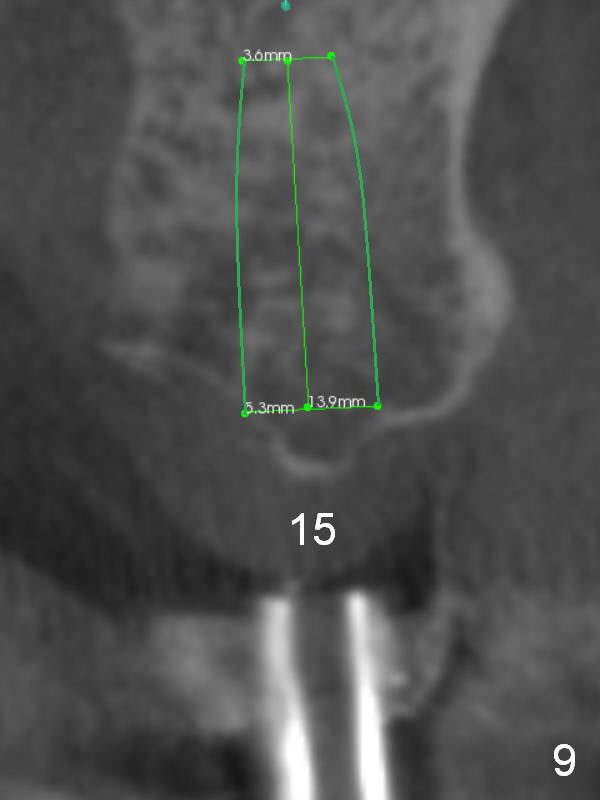

A 52-year-old man has multiple missing teeth. Since he has a lower partial denture (Fig.5), implants will be placed at the sites of #14 and 15 first (Fig.1). The site of #14 may need bone expansion if bone density is low, whereas the ridge at #15 is wide (Fig.2). There is no problem in height at the sites of #14 and 15 (Fig.3).

CBCT confirms that the ridge at #14 is narrower than that at #15. In contrast, the bone density is lower at #15 than that at #14 (Fig.7-9). If the keratinized tissue is wide, use 4 mm tissue punch (3 mm from #13). If incision is made, wheel saws will be used to split the ridge. Or use Magic split and osteotomes. Bone expanders are going to be used for bone expansion at #14 and bone condensation at #15 (Fig.8,9). Be careful while using bone expanders at #14, since the bone density is higher. There is a chance of plate fracture. Use drills if indicated. Fabricate splinted provisional after placement of abutments.